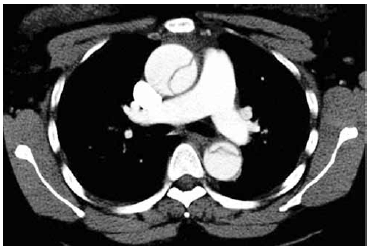

Homem de 67 anos relata início de dor torácica intensa há cerca de 4 horas. Refere histórico de hipertensão arterial e tabagismo, em uso de enalapril, hidroclorotiazida e anlodipino. Nega cardiopatia ou broncoespasmo. Ao exame físico: fácies de dor, consciente, orientado, sudorético e muito ansioso; PA: 195 x 115 mmHg, FC: 110 bpm, FR: 20 ipm e SatO2: 93%. Exames gerais, d-dímeros, troponina de alta sensibilidade, BNP e gasometria arterial são solicitados; tomografia multidetector realizada é mostrada a seguir.

Constitui uma complicação que é mais provável nesse paciente: